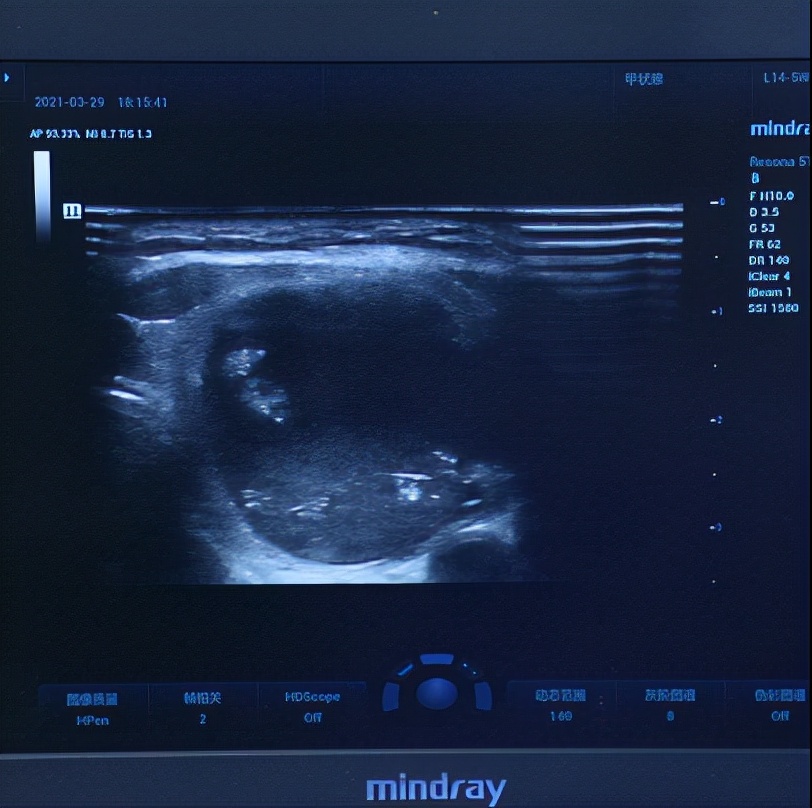

四维彩超报告出来后,显示涂女士的甲状腺体积已经增大,呈现出弥漫性病变,这个是由于涂女士甲亢病程较长导致的。

还有一个8.5mm的囊实性结节,这个结节的等级是3级,良性结节的可能性比较大。